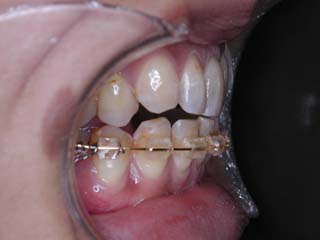

この症例では、上顎にリンガルブラケット矯正装置(Kurz)が用いられています。

使用した主な装置名:TPB、上顎リンガルブラケット矯正装置、下顎マルチブラケット装置、オーソアンカー SMAPシステム

本症例について検査診断の結果、開咬、叢生、下顎前突傾向を認めました。患者希望を考慮し、治療メカニクスとして、非抜歯配列、上顎のみリンガルブラケット矯正装置、下顎唇側マルチブラケット矯正装置、および、目的外使用のオーソアンカー SMAPシステムを用いることにいたしました。